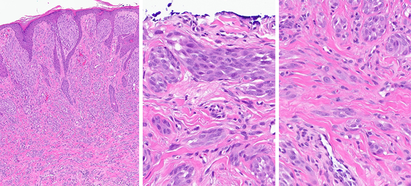

MyPath Melanoma

Learn about Castle’s comprehensive diagnostic offering

Our suite of objective and highly accurate tests for melanocytic lesions of uncertain potential increases diagnostic confidence and enables better clinical management plans for patients. Learn the essentials from this comprehensive introduction by Matthew Goldberg, MD, Senior Vice President, Medical for Castle Biosciences.